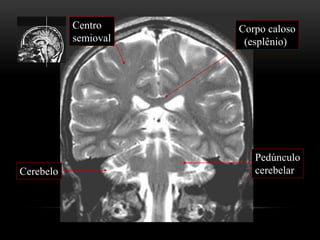

Corpo caloso

(esplênio)

Centro

semioval

Pedúnculo

cerebelarCerebelo

Cerebelo